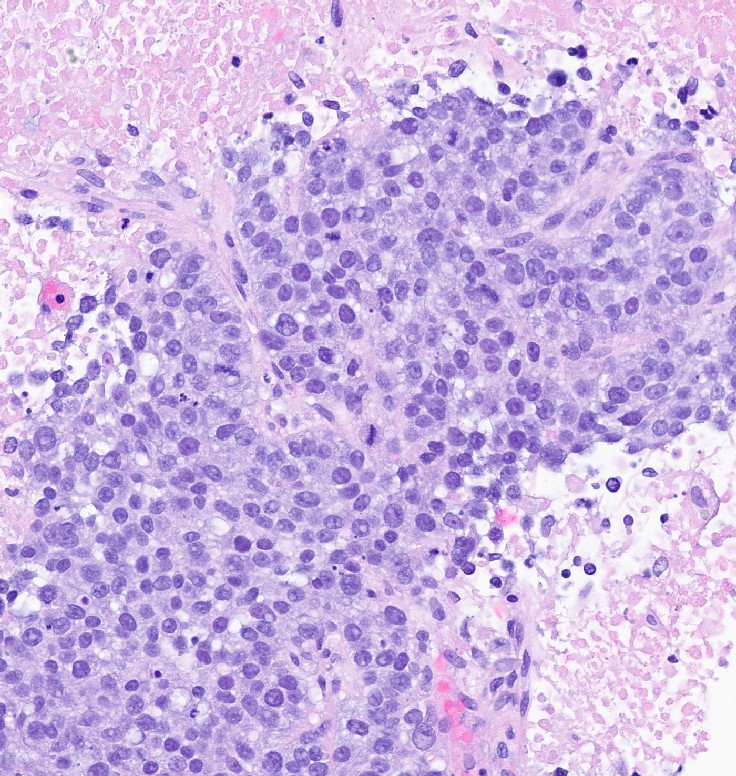

Microscopic (histologic) images

Contributed by Julie M. Jorns, M.D., Kristen E. Muller, D.O., Gary Tozbikian, M.D. and Emad Rakha, M.D.

- Histological features of IBC NST vary considerably from case to case and even within the same case

- Margins vary from highly infiltrative, permeating the surrounding tissue, to continuous pushing margins

- Architecture varies from sheets, nests, clusters, cords or individual cells (but lacks the cytomorphological characteristics of invasive lobular carcinoma)

- Tubular formations are prominent in well differentiated tumors but absent in poorly differentiated tumors

- 2 distinct growth patterns exist:

- Large and solid nests or syncytial infiltrative growth pattern with little associated stroma and an expansive growth that compresses the surrounding stroma (e.g., most basal-like breast cancers)

- These tumors typically show high histological grade, a prominent tumor associated lymphocytic (TIL) infiltrate, a triple negative phenotype and often have basal-like molecular profiles